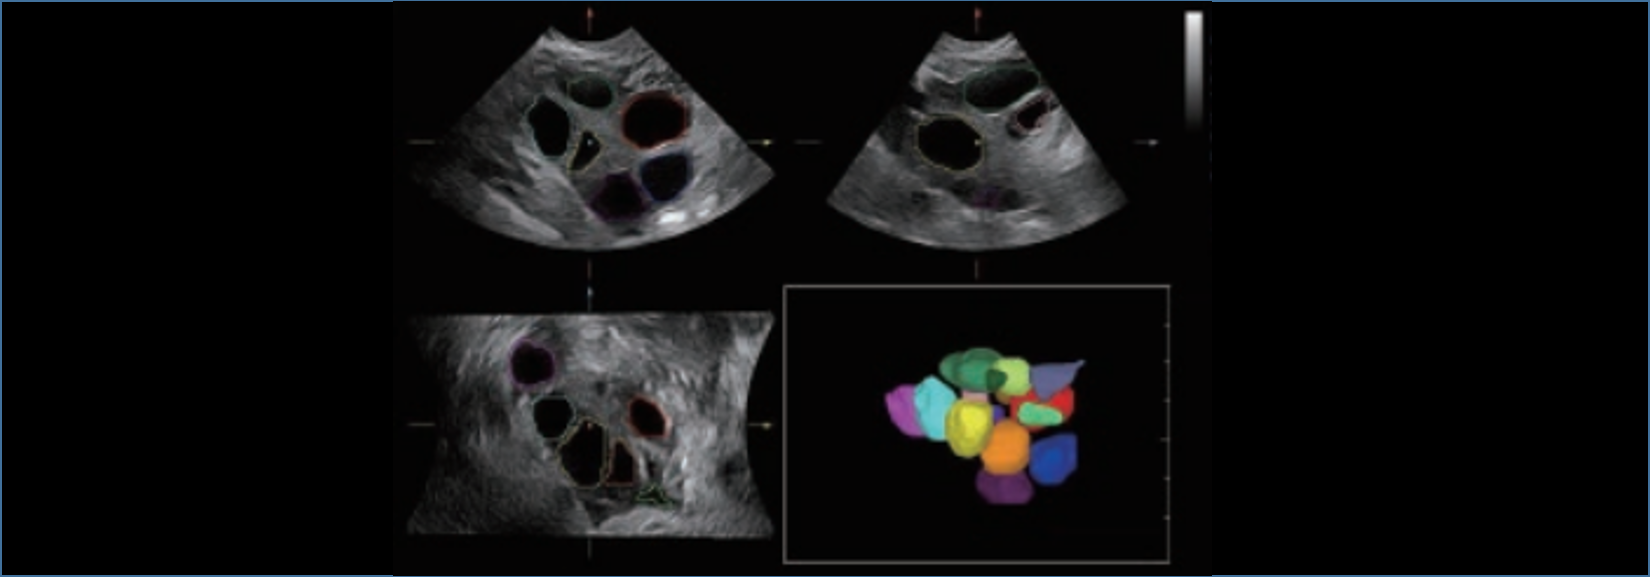

Resona 7, ĂŒstĂŒn dĂŒzeyde g?rĂŒntĂŒ kalitesine ek olarak, vaskĂŒler hemodinamik de?erlendirmesi i?in devrim niteli?indeki V Ak??? ile fetĂŒs CNS tan?lamas? i?in 3 boyutlu veri kĂŒmesinden dĂŒzlem g?rĂŒntĂŒsĂŒ alma konusunda en iyi birime sahip oldu?undan, klinik ara?t?rma yeterliklerini de art?rmaktad?r. En sezgisel, harekete dayal? ?oklu dokunmatik i?letim ile tĂŒm temel klinik ?zellikleri bir araya getiren Resona 7, ultrason yenili?i konusunda ger?ek anlamda yeni dalgalara ?ncĂŒlĂŒk ediyor.